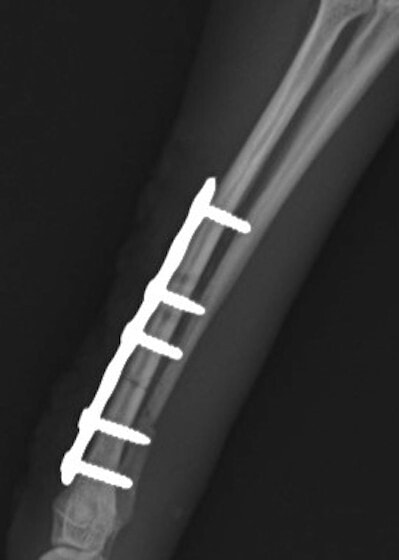

トイプードル 右遠位橈尺骨短斜骨折のALPSによる内固定

Locking Compression Plate

LCPは、スクリュー(ネジ)とプレート(金属の板)をロックする特殊な構造により骨折部位を固定する新しい世代のプレートシステムです。ひとつのホールでロッキングスクリューとスタンダードスクリューの使用を選択できるユニークな構造をしているため、骨折断端間の圧迫を目的とした従来型プレート固定法に加え、高い角度安定性を有するロッキングスクリューを用いた固定法の選択が可能です。従来のプレートシステムでは困難だった部分の骨折や癒合不全の症例に高い治療効果をもたらします。